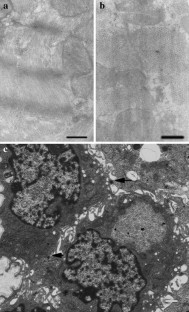

Icariin, the primary active component of Epimedium extracts, has recently been shown to induce cardiomyocyte differentiation of murine embryonic stem (mES) cells in vitro. However, as these cardiomyocytes were not functionally characterized, the potential application of icariin-induced cardiomyocytes in clinical practice remains unclear. Therefore, in this study, we characterized the structure and function of icariin-induced cardiomyocytes to evaluate their potential application in transplantation for cardiac failure treatment. mES cells were cultured as embryoid bodies (EBs) via the direct suspension method in the presence of icariin. The protein expression profiles and ultrastructural characteristics of mES cell-derived cardiomyocytes were then characterized by immunofluorescence and transmission electron microscopy, respectively. In addition, the expression of cardiac-specific and calcium handling genes was detected by semi-quantitative reverse transcription-polymerase chain reaction (RT-PCR). Cardiomyocytes induced by icariin treatment expressed the cardiac-specific proteins myosin light chain-1v (MLC1v), atrial natriuretic polypeptide (ANP), and cardiac troponin I (cTnI). Furthermore, these cells appeared to possess myofibrils organized into mature sarcomeres that had formed A and I bands. In addition, icariin treatment upregulated the mRNA levels of MLC1v, ANP, cTnI, calsequestrin (CSQ), and sodium–calcium exchanger (NCX) in these cells. Icariin induces the differentiation of mES cells into beating cardiomyocytes with normal structure and function. Therefore, these cells may have promising applications in cardiac cell therapy or tissue engineering.